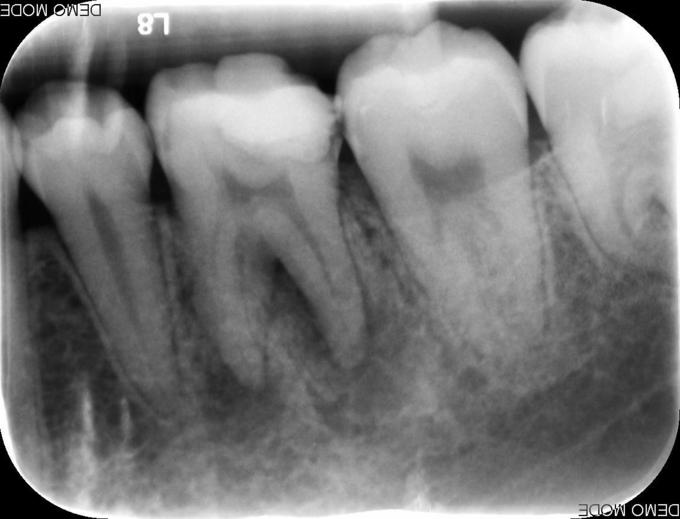

主诉:左下后牙咬物不适半年余 现病史:患者自诉半年年前左下后牙开始出现咬物不适,无自发痛、夜间痛,无放射到颌面部,今至我科就诊要求治疗

检查:#36 he 面见白色充填物,叩(+),松(-),咬合痛,冷热测无反应,电测无活力,牙龈稍红肿。余牙未见明显异常 X线示:#36根尖周有阴影

诊断:#36慢性根尖周炎 治疗:#36开髓、揭顶,拔髓,冲洗,测量WL,根管预备,封Ca(OH)2两周,ZOE暂封。两周后复诊去暂封,冲洗根管,测WL,试尖,根充。